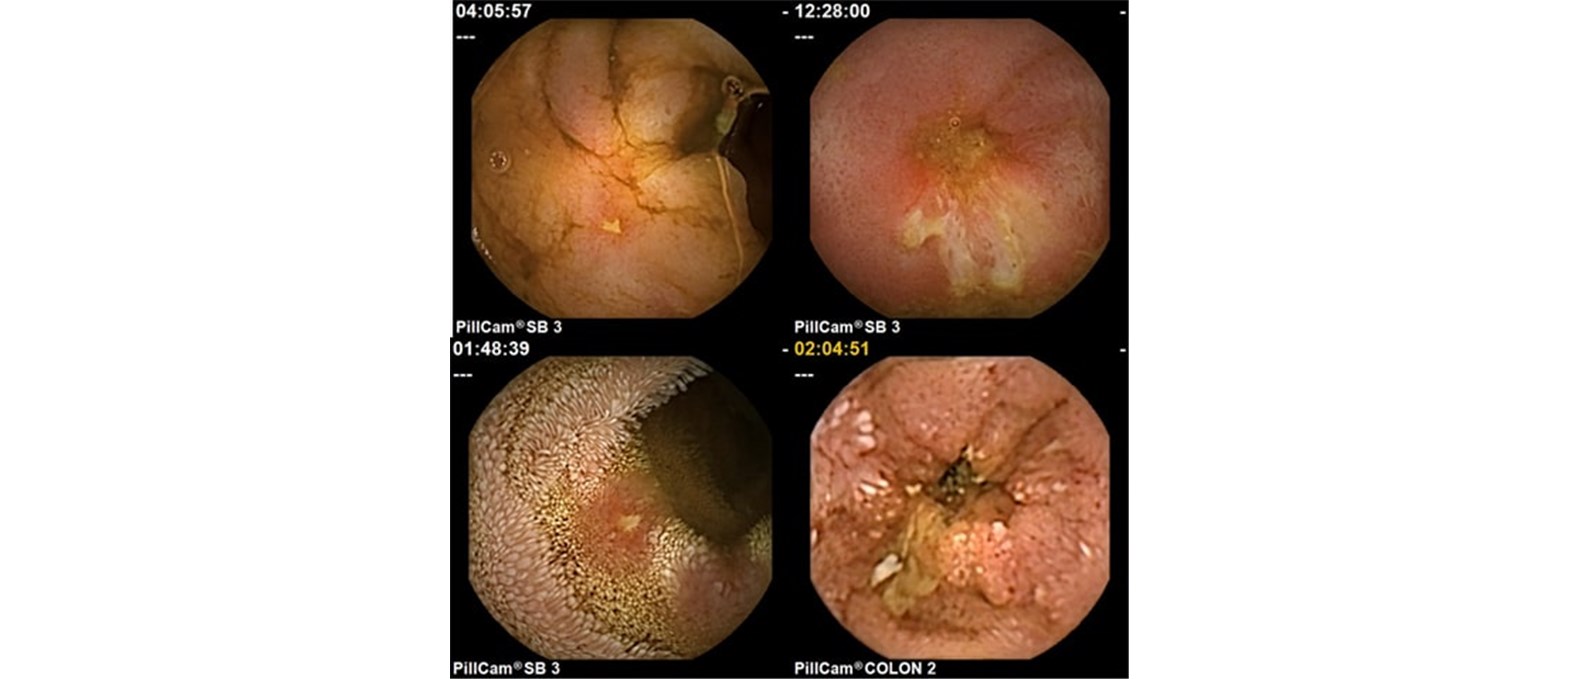

א. גלולת מעי דק (SB3) המיועדת לבירור דמם סמוי ממערכת העיכול, חשד למחלת קרוהן, מעקב אחרי מחלת קרוהן ועוד.

ב. גלולת מעי גס (ColonCapsule) המיועדת לסקירת מעי גס כתחליף לקולונוסקופיה בחלק מהמטופלים.

ג. גלולת קרוהן (PillCam Crohn’s Capsule) הסוקרת גם את המעי הדק וגם את המעי גס. מדובר בגלולה החדשה ביותר מבין השלוש, ששיווקה החל בימים אלה. הגלולה מיועדת לאבחון ומעקב אחרי מחלת קרוהן בלבד.

הקפסולה רגישה מאוד בגילוי דלקת במעי דק. למעשה רגישותה גבוהה יותר מאשר כל אמצעי אבחנתי אחר (קולונוסקופיה, MRI, CT ועוד). מלבד גילוי, הקפסולה מאפשרת מעקב אחרי דלקת במחלת קרוהן באמצעות בדיקות חוזרת (למשל, במטרה לוודא שהטיפול התרופתי אכן מביא לריפוי הדלקת במעי).

קפסולת קרוהן החדשה, העתידה להיכנס לשימוש בחודשים הקרובים, צפויה לחולל מיני מהפכה באבחון ומעקב אחרי מחלת קרוהן. היות וגלולה זו סוקרת גם את המעי הדק וגם את המעי הגס, היא תוכל במקרים רבים להחליף לפחות 2 פעולות אבחנתיות – גם קולונוסקופיה (אלא במקרים בהם נדרשת ביופסיה או פעולה טיפולית) והן בדיקות הדמיה כגון MRI ו-CT. הקפסולה החדשה מאפשרת להציג מעין "מפה" של המחלה במערכת העיכול, עם ציון של חומרת הדלקת בכל מדור של מערכת העיכול. במידה ומבוצעות בדיקות חוזרות, ניתן לעקוב אחרי שינויים במפה המשקפים את התגובה לטיפול או התקדמות המחלה.